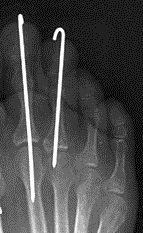

K wire fixation

- retrograde K wire out through P2 and P3 first

- back through P1, rest against subchondral bone

- check K wire position with image intensifier

- bend wire over and tape